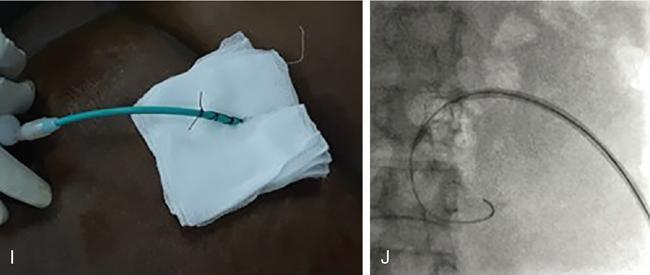

NONVASCULAR RENAL INTERVENTION Amitha Vikrama Nonvascular renal interventions have come a long way and have significantly reduced the surgical mortality and morbidity. It also paves way for short hospital stay and thus reducing the chances of nosocomial infection. They are usually pinhole or keyhole procedures with less distortion of the anatomy and physiology. They vary from image-guided aspiration/biopsy to percutaneous nephrostomy to complex procedures like ureteric stenting, strictureplasty, percutaneous nephrolithotomy etc. Iversen and Brun were the first to perform percutaneous renal biopsy of native kidneys in 1951. Over the years, newer imaging and biopsy techniques have evolved which have increased the biopsy yield to >95% and significantly reduced the complications of renal biopsy, resulting in decreased mortality rates from 0.12% to 0.02% during the last 50 years NOTE: Solitary renal mass lesions suspicious for malignancy should not be subjected to percutaneous biopsy, as there are chances of tumour seeding along the biopsy track. Excision biopsy is preferred for those lesions as it can be curative. USG-guided renal biopsy is the preferred method over blind biopsies. It avoids nontarget biopsies and reduces bleeding risks. Usually the lower pole of the kidneys is preferred site in native renal biopsy. The needle has to be directed into the lower cortex and care taken to avoid renal medulla and collecting system. 18G trucut biopsy needles are usually used in adults. In paediatric population, 20G can be used. Rarely, Coaxial technique is used in very obese patients and in those who are unable to lie prone. It is usually done as an inpatient procedure. Four hours of fasting is required to prevent aspiration of gastric contents during the procedure. Antiplatelets and anticoagulants are stopped at least 3–5 days prior. Informed written consent has to be taken after explaining the risks and benefits of the procedure. Patient is to be positioned in prone and USG-guided marking of the site of biopsy done prior to cleaning and draping. The depth of the renal cortex from the skin surface has to be noted. If the ribs are coming in line with the lower pole cortex, then a cranially angulated path is preferred. After infiltration of 2% lignocaine, the biopsy needle is advanced up to and not into the lower pole cortex. As the kidney keeps moving with respiration, the biopsy should be properly timed to avoid hitting the collecting system and medulla. This method is real-time ultrasound guided renal biopsy (Fig. 10.21.1.1). There is another method practiced in few of the institutes where the location of lower pole of the kidney is marked on the skin after ultrasound screening. The marking corresponds to the lower most renal cortex at the end of normal inspiration and the biopsy path will be perpendicular to the bed without any craniocaudal or mediolateral angulation. The distance between the skin and the renal cortex is measured. The patient will be instructed strictly not to change his position. Then the biopsy will be done blindly without any real time USG guidance. With this method, more number of patients can be biopsied in a short interval time. In a transplanted kidney, which is usually grafted in the iliac fossa, biopsy can be obtained from upper or lower pole. Points to remember: Cortical tangential and cortical non tangential approaches have been described (Fig. 10.21.1.2). Cortical tangential approach is described to have better diagnostic yield with lesser complications. In this approach, the needle track will be almost parallel to the capsule so that only the cortical tissue is targeted (Fig. 10.21.1.3A–C). Renal biopsy can also be done with coaxial technique. In this method, a coaxial needle, one size bigger than the biopsy needle, usually 17G, is inserted up to the renal capsule. The stylet is then removed and the 18G biopsy needle is inserted through the coaxial needle and the required number of biopsy specimens obtained. After this, the rent in the capsule can be sealed off with gelatine plugs before removing the coaxial needle. This helps in preventing bleeding complications. In patients with high risk of bleeding due to coagulation abnormalities, transjugular renal biopsy can be done in which renal vein is cannulated and biopsy done from within (Fig. 10.21.1.3D–F). In obese patients who cannot lie prone, biopsies are done in lateral or oblique lateral positions under CT or USG guidance. CT guidance is especially helpful when the visualization of the kidney is difficult on ultrasound. In these cases, coaxial technique is always helpful. In 2019, KHA-CARI guidelines were first published for renal biopsy. A few of the salient recommendations are given below: It is an image-guided procedure in which the renal pelvicalyceal system is accessed percutaneously which is predominantly used for decompressing an obstructed system and also for various other therapeutic procedures. It is usually done under local anaesthesia and IV sedation. Major procedures might require general anaesthesia. All routine preprocedural blood tests and coagulation profile should be done. Appropriate antibiotics are administered intravenously prior to the procedure. 21G needle, 018 and 035 wires, appropriate dilators, sheath and pigtail drainage catheter. Ultrasound and fluoroscopy is required for guidance. Patient is usually positioned prone on the table. Under special circumstances, lateral or oblique positions are also used. After instillation of local anaesthesia, a 21G needle is used to access the renal calyx under USG guidance. Once the urine flow is seen, nonionic contrast is injected to delineate the renal collecting system. A 018 wire is passed through the needle into the pelvicalyceal system and later exchanged for a 035 wire. Appropriate tissue dilators are used to dilate the track before placing a pigtail drainage catheter. The drain is secured by stay sutures and connected to a urobag. The initial urine sample is to be sent for culture and sensitivity (Figs. 10.21.1.4–10.21.1.6). Ureteric stenting was first described by Zimskind et al endotracheal tube al in 1967. It is one of the commonest procedure done in urology practice It is usually done after doing a percutaneous nephrostomy. The percutaneous nephrostomy (PCN) drain is replaced with a 6F or 8F sheath over a guidewire and ureterogram is obtained to assess the site of stricture or obstruction. Using a catheter and guide wire combination, the stricture is negotiated and the exchange length hydrophilic wire is parked in the bladder. The ureteric length is measured and appropriate-sized double J (DJ) stent is inserted over the wire. Care is taken to get the loops formed at both ends of the DJ stent so that stent migration is prevented (Fig. 10.21.1.7). A variety of delivery systems are available for the deployment of the ureteric stent exist: pusher mechanism, string release and sheath (similar to an inferior vena cava (IVC) filter). Post stent insertion, the nephrostomy drain can be retained for a couple of days. The drain is closed externally and USG screening is done the next day to confirm antegrade flow after which the drain can be removed.